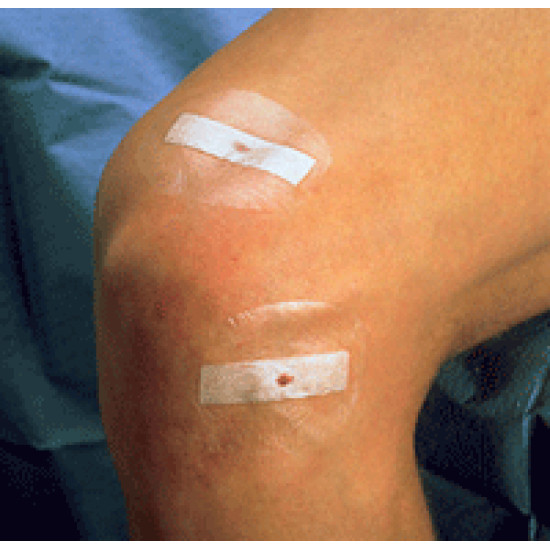

ЗМ™ Steri-Strip™ Wound Closure System - матеріал для безшовного закриття ран

Бесшовне закриття ран

Універсальна наклейка для закриття проколів та ран являє собою об'єднання єднану в єдине ціле липку стрічку Steri-Strip™ та плівкову наклейку Tegaderm™. Система дозволяє швидко та легко закрити хірургічні розрізи та проколи, повністю захищає рану від забруднення та інфекцій, не заважає диханню шкіри. Пацієнт може вільно рухатись та приймати водно-гігієнічні процедури. Система використовується для закриття дрібних ран, лапароскопічних проколів.

- Спочатку краї рані зводяться стрічкою Steri-Strip, потім накладається прозора плівка Tegaderm.